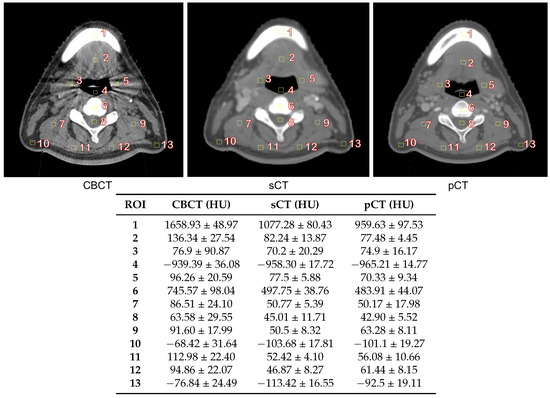

3.2. Image Quality Evaluation in Preserving Anatomy